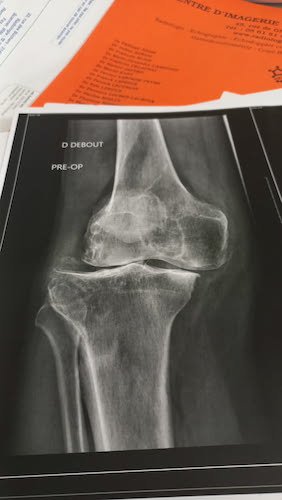

Figurez-vous qu’après Daniel ( viewtopic.php?t=2333 ), j’ai rencontré Miguel qui m’a donné 2 photos de son genou opéré. Une prise AVANT l’opération et l’autre APRÈS.

La photo du genou de Miguel AVANT.jpg

La photo du genou de Miguel AVANT.jpg (19.88 Kio) Vu 4138 fois